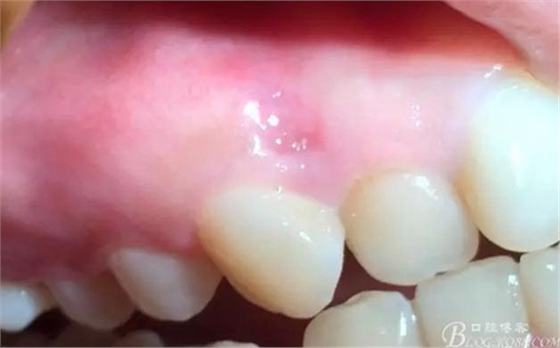

檢查:口腔衛(wèi)生尚佳,軟垢少量,牙石(+),色素沉著少量,全口牙齦色粉,質(zhì)地韌,BOP(+-),BI=0-1,全口PD=1-3mm左右,12,13唇側(cè)附著齦根尖方向處可見圓形色素沉著區(qū)(墨水沉積所致),其余黏膜以及唇紅未見異常,全口牙列未見明顯齲損。

術(shù)前

0.8*17mm工作尖 100mj 20Hz去除上皮,暴露著色區(qū)